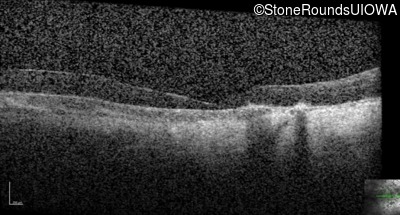

Optical Coherence Tomography - Right - No Light Perception

Exemplar / OCT Stack